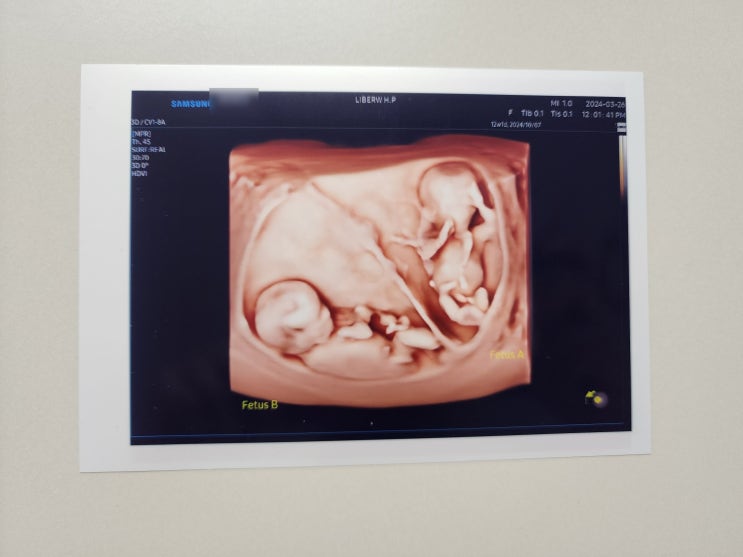

쌍둥이 임신기록(21-24주차) :: 튼살, 태동, 부종, 코피, 갈비뼈통증, 빨래시작

21주차 :: 농협아이적금, 허리통증 ✔️ 태동 : 태동으로 배가 아픔... ✔️ 배둘레 : 86cm, 33.8인치 ✔️...